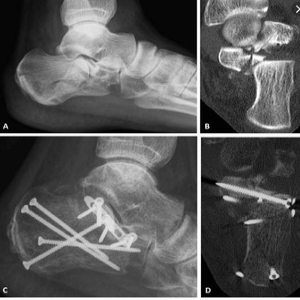

We Provide Best Orthopedic Surgeon in Nagpur